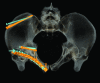

Methods: 7 patients (5 male and 2 female; median age 53 y (25 to 92 y)) with an acetabular fracture were prospectively included. Exclusion criterions were simple wall fractures, cases with anticipated surgical dislocation of the femoral head for joint debridement and accurate fracture reduction. According to the Letournel classification 4 cases had two column fractures, 2 cases had anterior column fractures and 1 case had a T-shaped fracture including a posterior wall fracture.The workflow included following steps: (1) Formation of a patient-specific bone model from preoperative computed tomography scans, (2) interactive virtual fracture reduction with visuo-haptic feedback, (3) virtual fracture fixation using common osteosynthesis implants and (4) measurement of implant position relative to landmarks. The surgeon manually contoured osteosynthesis plates preoperatively according to the virtually defined deformation. Screenshots including all measurements for the OR were available.The tool was validated comparing the preoperative planning and postoperative results by 3D-superimposition.

Results: Preoperative planning was feasible in all cases. In 6 of 7 cases superimposition of preoperative planning and postoperative follow-up CT showed a good to excellent correlation. In one case part of the procedure had to be changed due to impossibility of fracture reduction from an ilioinguinal approach. In 3 cases with osteopenic bone patient-specific prebent fixation plates were helpful in guiding fracture reduction. Additionally, anatomical landmark based measurements were helpful for intraoperative navigation.